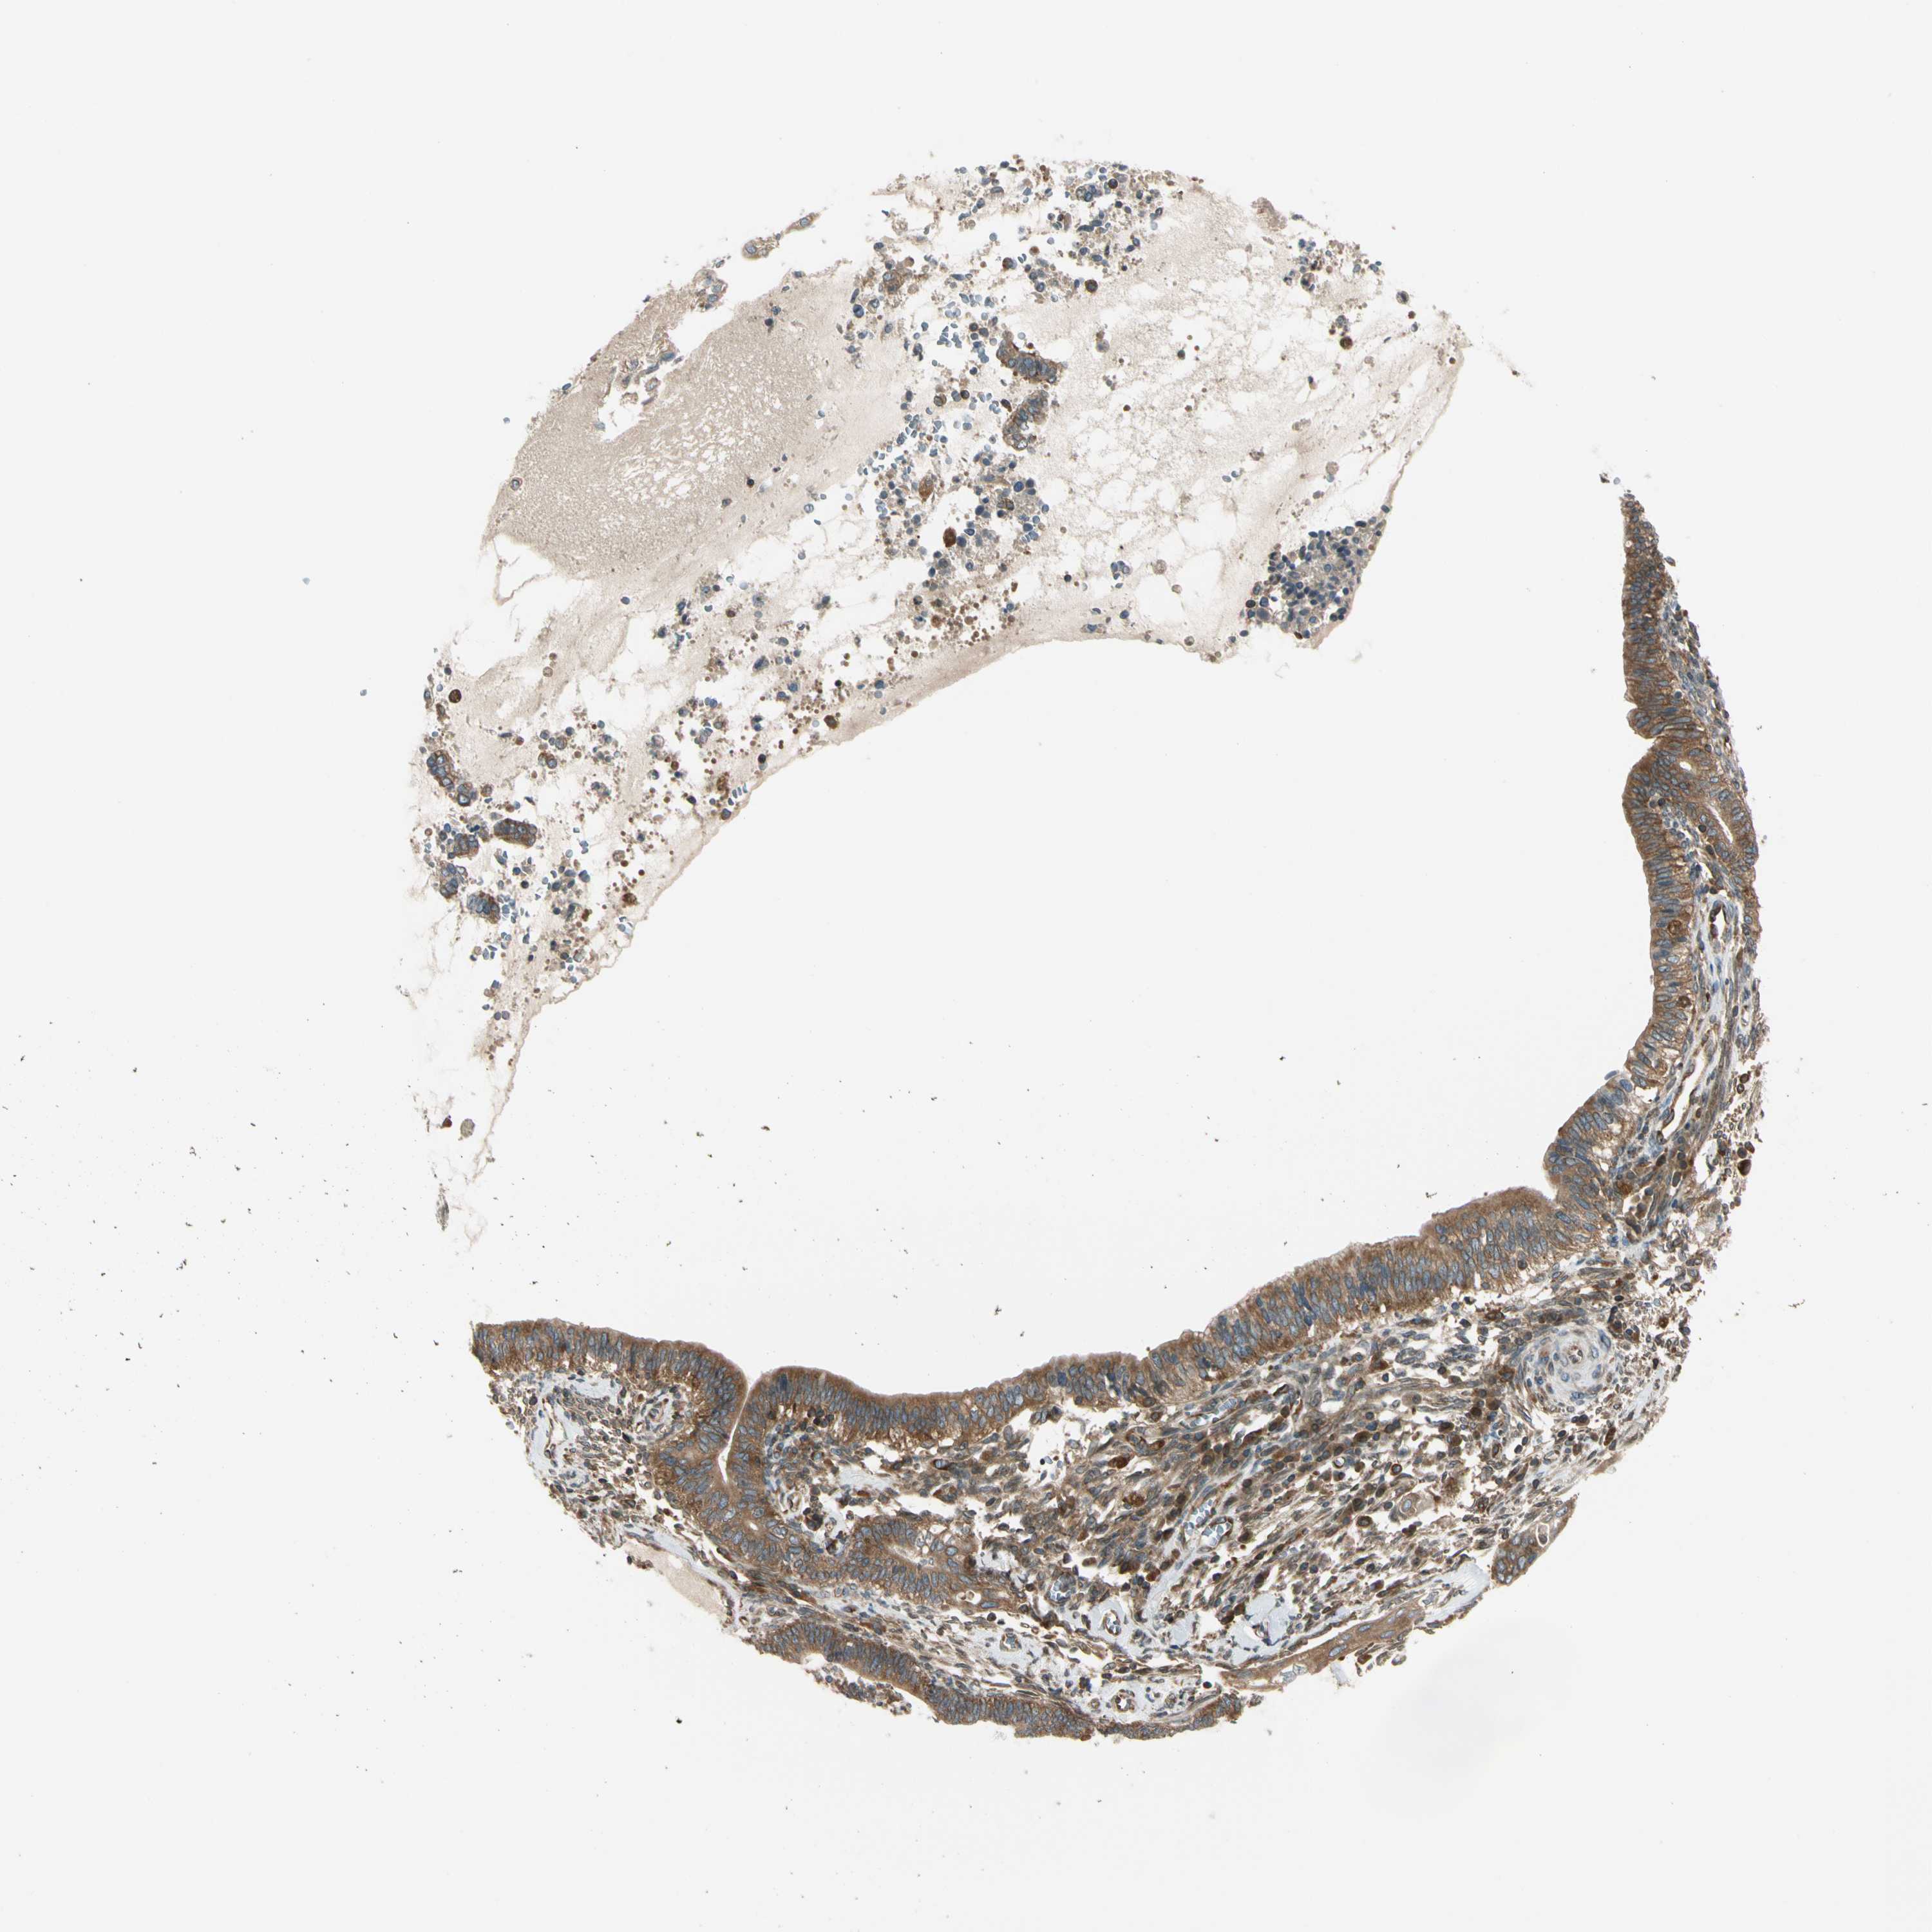

CERVICAL CANCER - Protein expressioni

A mouse-over function shows sample information and annotation data. Click on an image to view it in a full screen mode. Samples can be filtered based on level of antibody staining by selecting one or several of the following categories: high, medium, low and not detected. The assay and annotation is described here.

Note that samples used for immunohistochemistry by the Human Protein Atlas do not correspond to samples in the TCGA dataset.

Antibody stainingi

Antibody staining in the annotated cell types in the current human tissue is reported as not detected, low, medium, or high, based on conventional immunohistochemistry profiling in selected tissues. This score is based on the combination of the staining intensity and fraction of stained cells.

Each image is clickable and will lead to virtual microscopy that enables deeper exploration of all samples and also displays staining intensity scores, fraction scores and subcellular localization as well as patient and tissue information for each sample.

Antibody HPA008157

Staining

High

Medium

Low

Not detected

Intensity

Strong

Moderate

Weak

Negative

Quantity

>75%

75%-25%

<25%

None

Location

Nuclear

Cytoplasmic/membranous

Cytoplasmic/membranous,nuclear

Squamous cell carcinoma, NOS

Adenocarcinoma, NOS